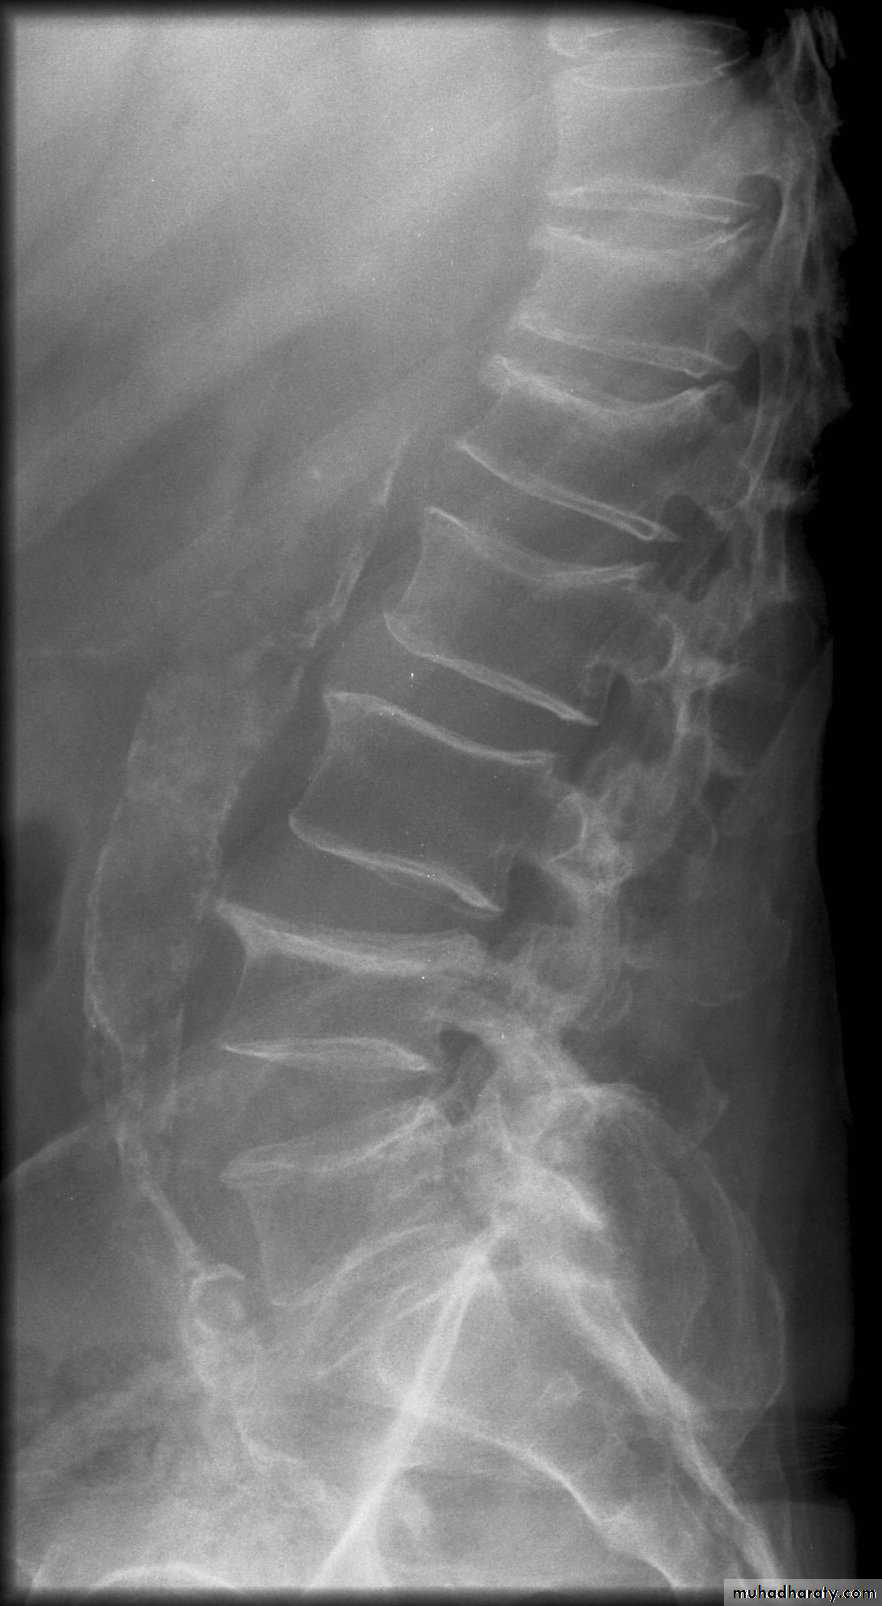

Vertebral bodies show earliest changes:

resorption of horizontal trabeculae

Empty box vertebra: apparent increased density of vertebral endplates due to resorption of spongy bone

Vertebral body compression fractures: wedge, biconcave codfish bodies, true compression

* Rugger jersey spine

rugger jersey spine